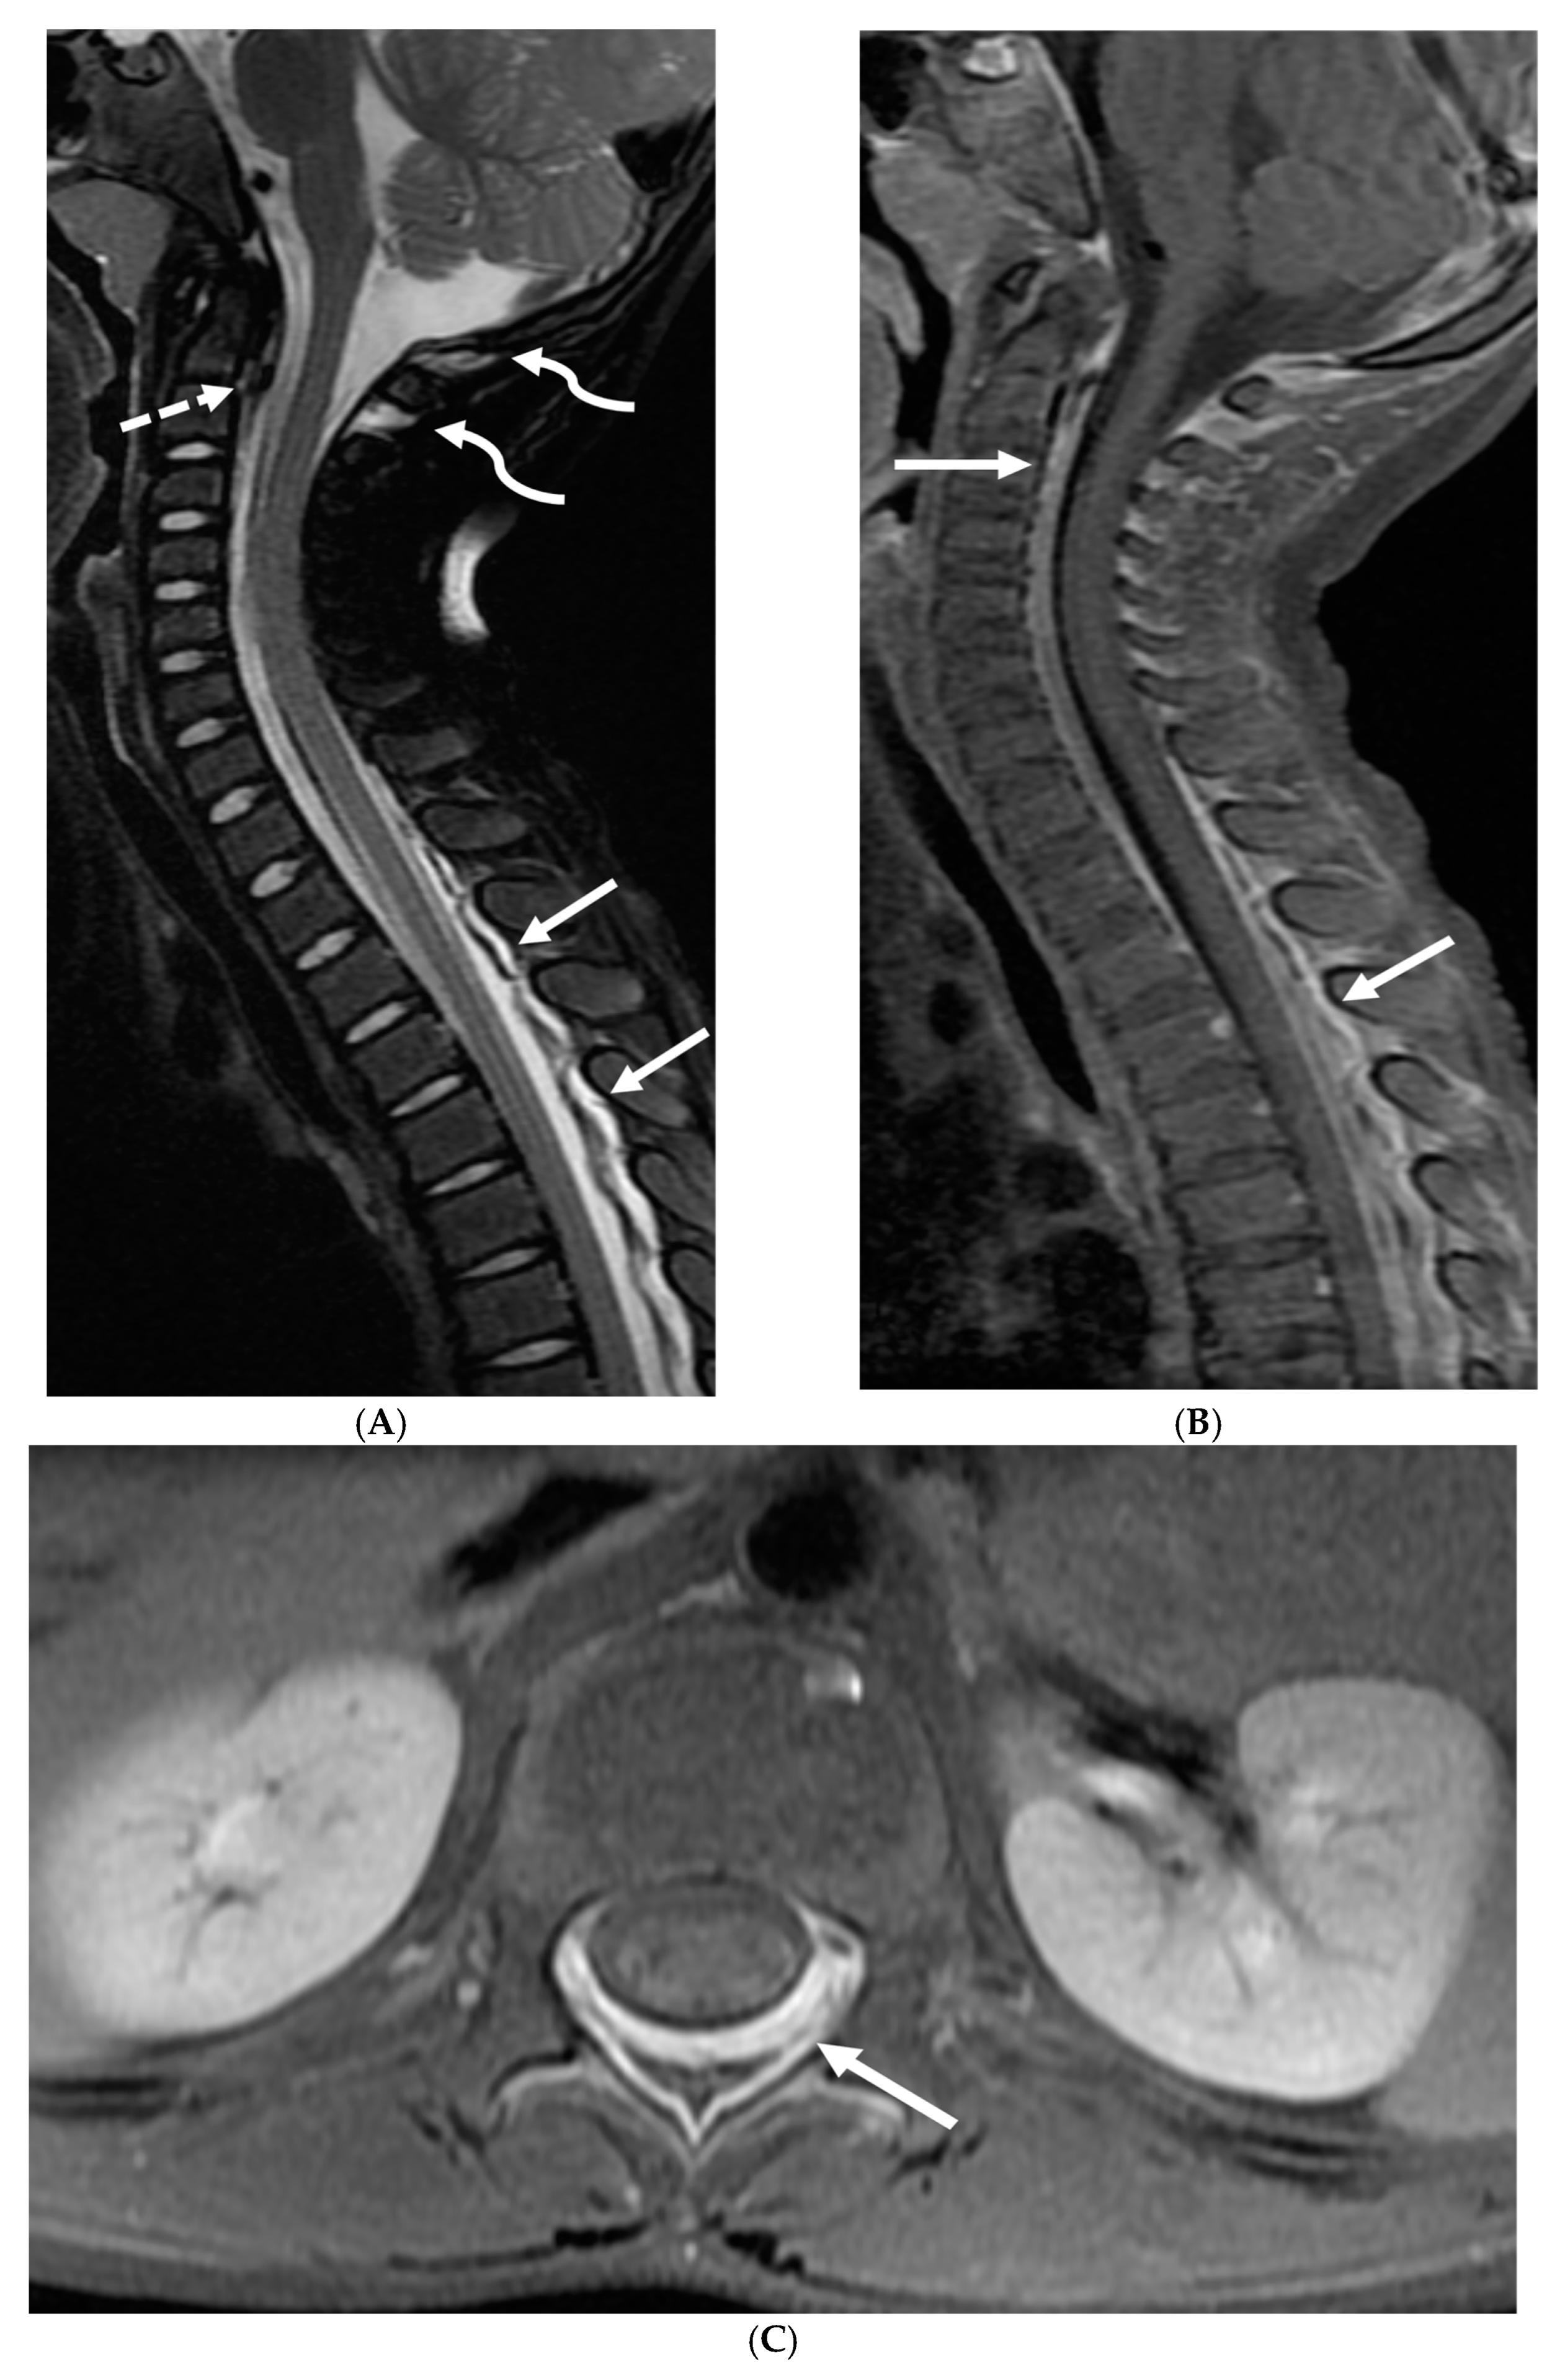

With regard to spine imaging, in addition to the intracranial features of dural enhancement, venous engorgement and subdural collection, unique findings include meningeal diverticula, dural ectasia and C1–C2 sign (Figure 8 and Figure 9). Additionally, a CT myelogram may identify the precise location of the CSF leak which can be sealed off with a blood patch [65,68].

Figure 9.

Sagittal T2 FS (A), sagittal (B) and axial (C) T1 post contrast: 3-year-old with neck pain post LP. There is diffuse epidural thickening, with increased T2 signal and enhancement, throughout the cervical, thoracic and lumbar spine (white arrows). Several prominent flow voids are seen within the anterior epidural thickening in the upper cervical region (dashed arrow). There is also increased high T2 signal between the occiput and posterior arch of C1, and between the posterior arch of C1 and spinous process of C2 (curved arrows) in keeping with “C1–C2 sign”. Findings are related to intracranial hypotension post lumbar puncture.